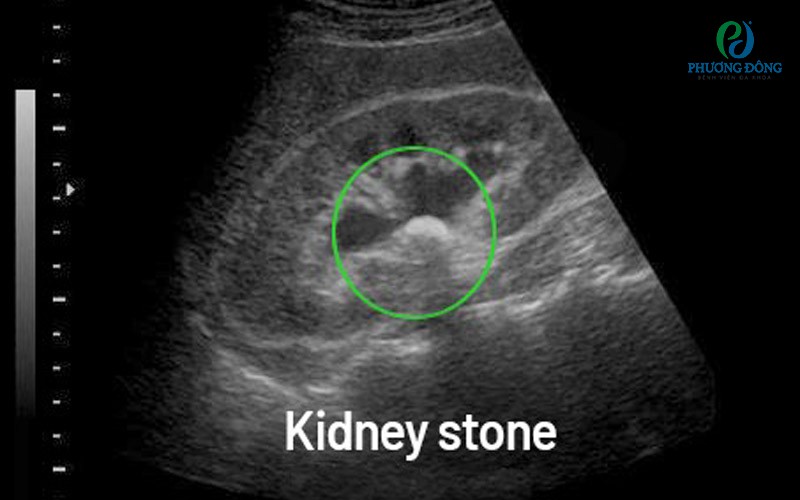

Hình ảnh siêu âm của thậnHình ảnh siêu âm của thận

Thận và hệ tiết niệu

• Bệnh lý: Sỏi thận, viêm thận, u thận, nang thận, viêm bàng quang, sỏi bàng quang, u bàng quang.

• Ý nghĩa: Giúp phát hiện nguyên nhân gây tiểu buốt, tiểu máu, đau lưng.